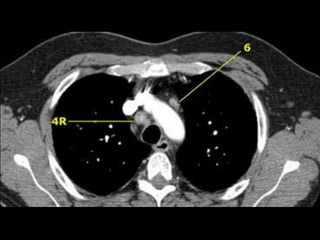

Ganglios

• Aórticos

– 5) Subaórticos: en la ventana aortopulmonar, laterales al

ligamento arterioso, próximos a la rama izquierda de la arteria

pulmonar.

– 6) Paraaórticos: en la cara anterior y lateral de la aorta

ascendente, el cayado y el tronco braquiocefálico.

• Mediatinales inferiores:

– 7) Subcarinales:

– 8) Paraesofagicos:

– 9) Del ligamento pulmonar

Ganglios • Aórticos – 5)Subaórticos: en la ventana aortopulmonar, laterales al ligamento arterioso, próximos a la rama izquierda de la arteria pulmonar. – 6) Paraaórticos: en la cara anterior y lateral de la aorta ascendente, el cayado y el tronco braquiocefálico. • Mediatinales inferiores: – 7) Subcarinales: – 8) Paraesofagicos: – 9) Del ligamento pulmonar